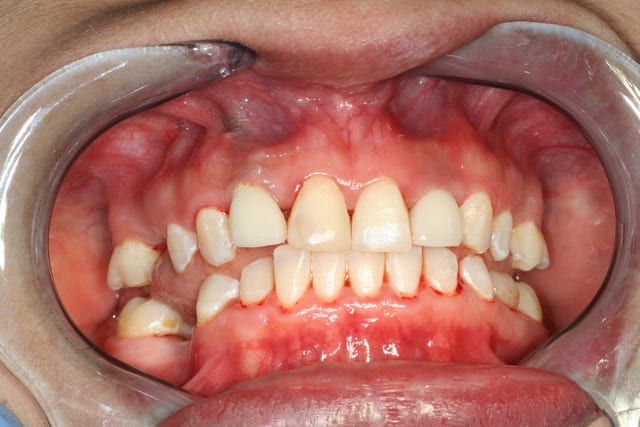

Cas intéressant.

Avec le peu d'éléments, difficile de bien juger le cas.

Agénésie, donc crête fine.

Biotype gingival?

Esthétique, sourire. Gestion des papilles?

Rôle de l'occlusion, elle semble être en supracclusion.

Déposer les implants en tout début, on risque de perdre pas mal d'os.

Une approche plus paro ne permettrait elle pas de gérer la situation?

Changer le biotype, épaissir la gencive et ROG pour 22. Sans oublier de vérifier l'occlusion. Eventuellement travail sur les prothèses (provisoires ++).

Qu'en pensez vous?

Donc laisser les implants en place et réaménager l'environnement, of course si les implants sont ostéointegrés et pas de foyer infectieux. bonne solution et pour le patient et pour le "cas". j'adhère